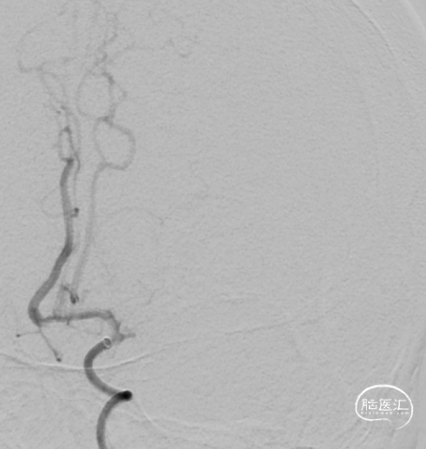

取栓后复查造影见左侧大脑中动脉仍闭塞。

再次将4.0*30mm Syphonet®取栓支架释放到位并造影,见左侧大脑中动脉狭窄段仍明显,且靠近豆纹动脉处。

考虑狭窄明显并夹层形成,遂行4.5*22mm 自膨式闭环支架于左侧大脑中动脉水平段并造影。